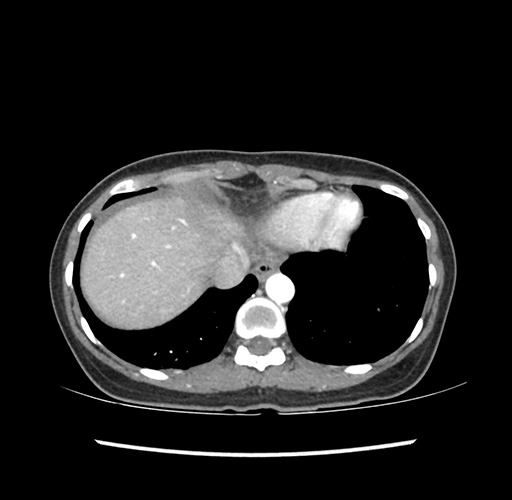

Imaging Analysis

Look through the patient's CT scan to identify any areas of concern for the necessary procedure.

Based on your CT findings, which issue(s) would give reason for "planned slowing down moment(s)" in this case?